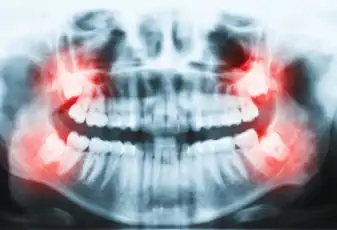

שן בינה כלואה

שן בינה כלואה - המדריך עם כל המידע הרפואי והמעודכן השיניים הטוחנות האחורית ביותר מכל צד של הלסת העליונה והתחתונה , מכונות גם "שיני בינה", זאת משום שהן בוקעות אל חלל הפה רק לאחר תום פרץ הגדילה של גיל הנעורים, דהיינו בסביבות